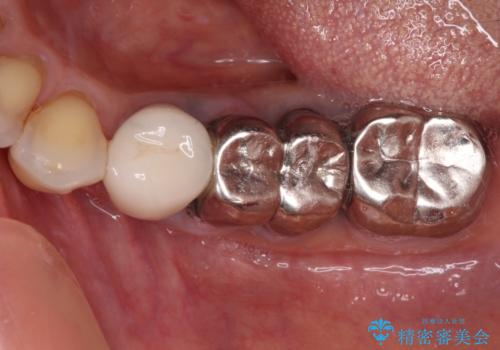

臼歯部メタルフリー再補綴